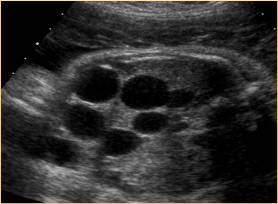

The typical ultrasound findings in MCDK include multiple anechoic cysts of different sizes and renal enlargement. [76]

In serial ultrasound follow-ups, an initial increase in the size and number of cysts is observed. This is followed by involutional changes, which persist during the pregnancy and into the neonatal period. [77]

The MCDK should be considered a progressive and changing pathology. The larger cysts appear in the early third trimester and after achieving a maximum size begin to regress to small non-cystic masses, which may eventually disappear. [78]

Above. Patient B. Unilateral MCDK. Multiple cysts of varying size and echogenic kidney. Contralateral kidney is normal.

Above. Patient C. Unilateral MCDK with multiple cysts of varying size and some dysplastic changes indicated by echogenic texture.